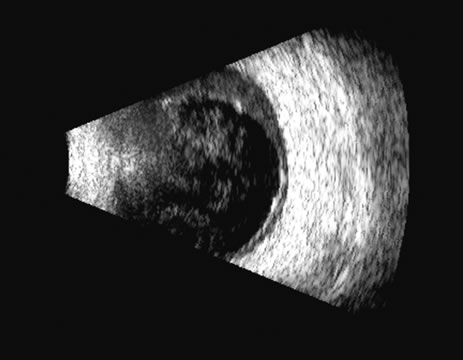

Fig. 2. Ciliary body retroiridal cyst can be demonstrated in this occult area as clear, usually rounded, single or multiple cystic spaces. They are nearly always clear acoustically and may at times contact the lens and occasionally cause cataract formation.

Fig. 3. Solid tumor of the ciliary body, often appearing relatively round, but occasionally irregularly shaped to match the area of the ciliary body itself. It can be presented in 3D for measurement of growth, but usually these highly lethal tumors are treated soon after presentation.